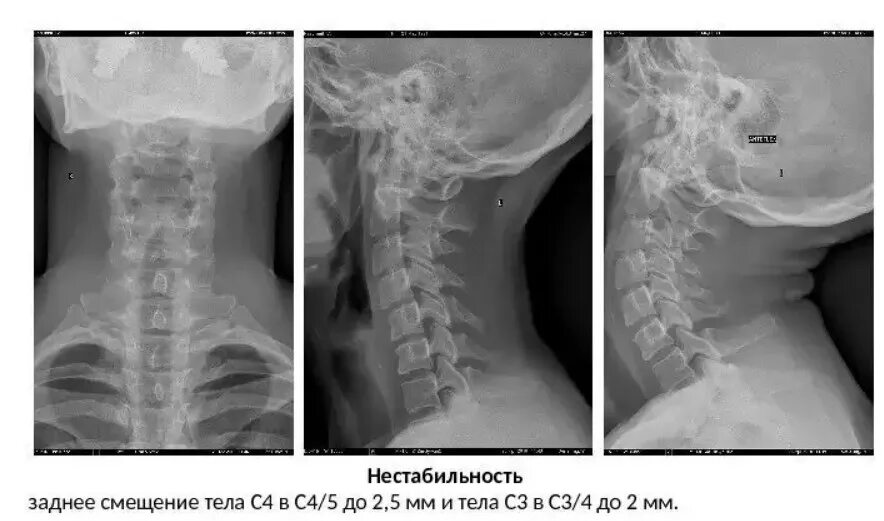

Нестабильность сегмента с3